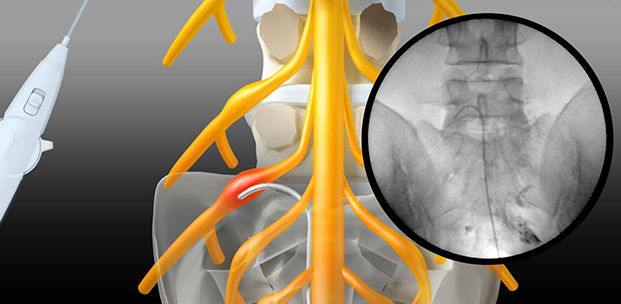

풍선확장술이란?

풍선확장술이란 방사선 기구를 이용하여 병변의 위치를 확인하면서

꼬리뼈 중앙 빈 공간을 통해 특수 카테터를 삽입합니다.

병변 부위까지 도달하면 풍선을 부풀려 협착 부위에 공간을 확보하고,

염증 치료 및 약물 주입으로 병변을 치료합니다.

풍선 신경성형술(PEN) 치료 과정

01. 국소 마취

C-ARM 영상 확인 하에 국소 마취 후,

엉치뼈 틈새를 통해 천골관으로 유도자 바늘을

삽입하여 조영제를 주입합니다.

03. 풍선확장술 시술

핸들링을 통해 카테터를 병변 부위까지

접근 시킨 후 풍선을 확장시킵니다.

협착공간을 넓힘으로써 유착을 풀어줍니다.

02. 카테터 삽입

특수 카테터를 경막외강을 통해

천천히 진입시킵니다.

04. 염증 해결

풍선을 다시 수축시킨 후 약물을 주입하여

염증 및 유착을 해결합니다.